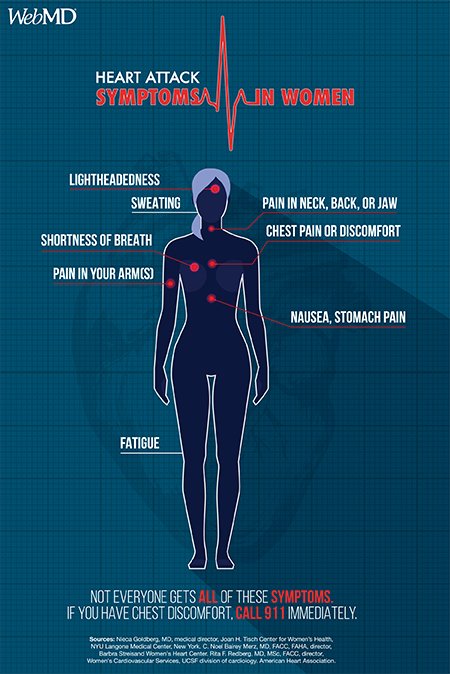

According to the CDC, heart disease is the leading cause of death for US women. Here's a look at the symptoms. http://wb.md/2j1B4HB pic.twitter.com/wnNoBxktc2